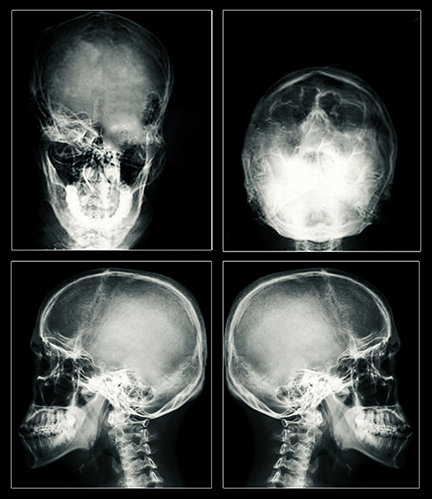

Resultatet forblir det samme: et grand mal epileptisk anfall og hjerneskade, som kan bli permanent. Den enormt økte elektriske strømmen som brukes i dag kan rive hull i hjerneceller, som dreper cellene. Elektrisiteten kan også drepe cellene ved å generere varme. MRI-er tatt av ECT-pasienter har vist arr i og krymping av hjernen – entydige bevis for alvorlig skade.